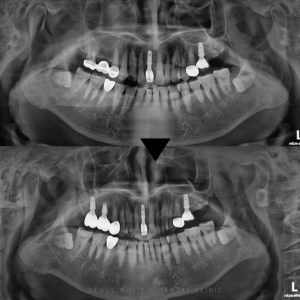

영도치과, 자연치와 조화를 이루는 임플란트 식립 사례 안녕하세요, 영도치과 서울화이트S치과입니다! 우리 치과에는 건강한 치아를 가지고 내원하시는 분들도 계시지만, 여러 치아에서 예후가 좋지 않은 징후가 나타나는 경우도 종종 있습니다.…